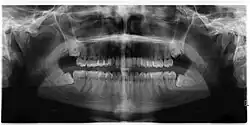

| Diagnostic method | Examination, x-ray |

Impacted wisdom teeth are classified by their direction of impaction, their depth compared to the biting surface of adjacent teeth and the amount of the tooth's crown that extends through gum tissue or bone. Impacted wisdom teeth can also be classified by the presence or absence of symptoms and disease. Screening for the presence of wisdom teeth often begins in late adolescence when a partially developed tooth may become impacted. Screening commonly includes a clinical examination as well as x-rays such as panoramic radiographs.

If the tooth cannot be assessed with clinical exam alone, the diagnosis is made using either a panoramic radiograph or cone-beam CT. Where unerupted wisdom teeth still have eruption potential several predictors are used to determine the chance of the teeth becoming impacted. The ratio of space between the tooth crown length and the amount of space available, the angle of the teeth compared to the other teeth are the two most commonly used predictors, with the space ratio being the most accurate. Despite the capacity for movement into early adulthood, the likelihood that the tooth will become impacted can be predicted when the ratio of space available to the length of the crown of the tooth is under 1.[5]: 141